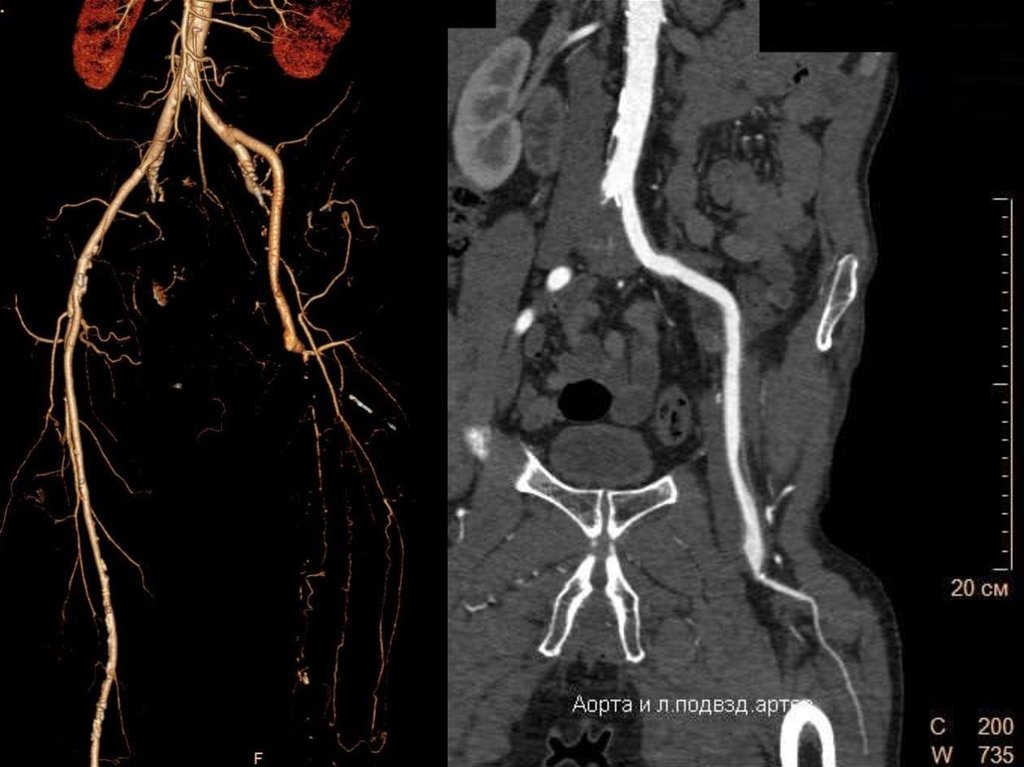

Распространенный

атеросклероз и

протяженная

окклюзия левой

бедренной артерии